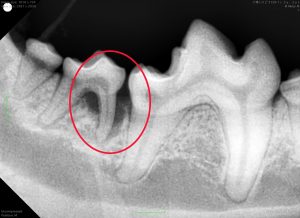

外から見ると一部に歯石が付着しているだけに見えます。 これだけ見ると「歯石除去だけで大丈夫」、あるいは「もう少し歯磨きを続けて様子を見ましょう」と言われてしまうかもしれません。しかし見た目と重症度が必ずしも一致しないのが歯周病の恐ろしいところです。 この子に関しても歯科レントゲン検査を実施したところ…

重度の歯周組織の破壊が見つかりました。放置しておけばさらに歯周炎が進行し、多数の抜歯が必要になっていたかもしれません。